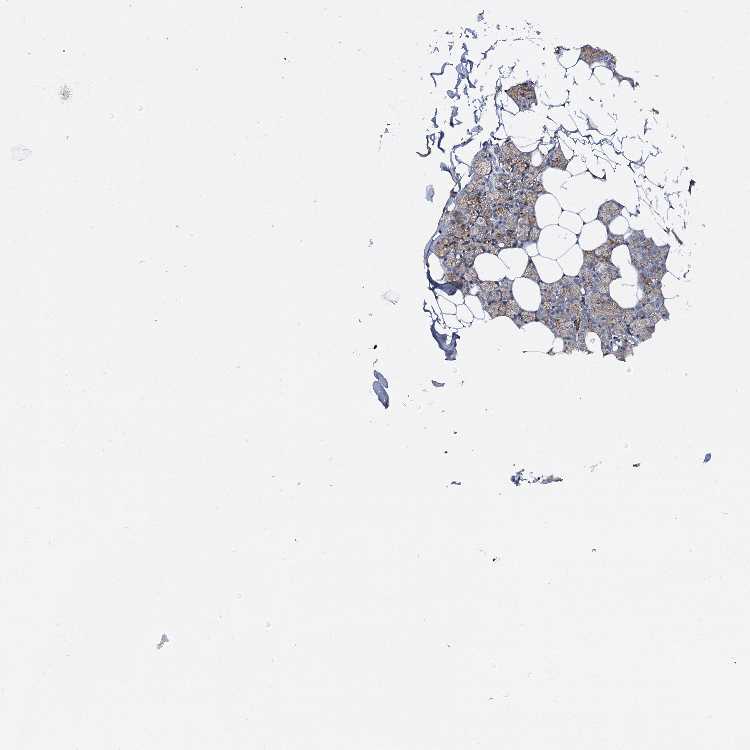

SALIVARY GLAND - Antibody stainingi

Antibody staining in the annotated cell types in the current human tissue is reported as not detected, low, medium, or high, based on conventional immunohistochemistry profiling in selected tissues. This score is based on the combination of the staining intensity and fraction of stained cells.

Each image is clickable and will lead to virtual microscopy that enables deeper exploration of all samples and also displays staining intensity scores, fraction scores and subcellular localization as well as patient and tissue information for each sample.

Antibody HPA006667Antibody CAB037171Antibody CAB037289

Glandular cells MediumHighHigh